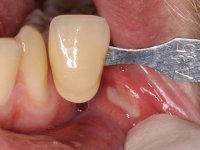

O paciente foi observado conjuntamente e a dúvida que surgiu de imediato foi se seria possível com a regeneração óssea a efectuar poder ser reabilitada naturalmente a zona das papilas interdentárias. Nesse sentido foi feito um enceramento de diagnóstico que contemplaria as duas hipóteses, utilizando ou não a cerâmica gengival. A confecção desse enceramento foi fundamental para expor ao paciente a dificuldade da reabilitação. O wax-up deu origem a um mock-up que foi aprovado pelo paciente e que simultaneamente serviu de guia imagiológica. O caso foi planificado cirurgicamente e realizada uma guia cirúrgica com que foram colocados os implantes. Após 10 semanas foi feita a 1ª impressão para confecção da ponte provisória. Foram criados os primeiros perfis de emergência na gengiva artificial e foi digitalizado o modelo. Por processo de CAD-CAM foi confeccionada uma ponte provisória aparafusada baseada no enceramento de diagnóstico. A ponte trabalhou durante 8 semanas os tecidos moles que foram fielmente copiados numa impressão com técnica de moldeira aberta. Os transferes foram individualizados com resina composta para copiarem fielmente os perfis de emergência criados pela ponte provisória. Confeccionado o modelo de trabalho definitivo, foi realizada uma infra-estrutura em zircónio seguindo a orientação do enceramento de diagnóstico. O assentamento da infra-estrutura foi testado em boca e simultaneamente foi novamente impressionados os tecidos moles com um silicone fluido. Nessa consulta foi feito o levantamento da cor. Os dentes 13 e 23 apresentavam uma saturação anormalmente forte que resolvemos não valorizar, optando por privilegiar a relação com o sector antero-inferior. Foi realizada uma nova gengiva artificial com a impressão que acompanhou a impressão de arrasto com a infra-estrutura. Após a colocação da cerâmica na infra-estrutura foram coladas as meso-estruturas. O trabalho final foi aparafusado lentamente permitindo a adaptação dos tecidos moles.